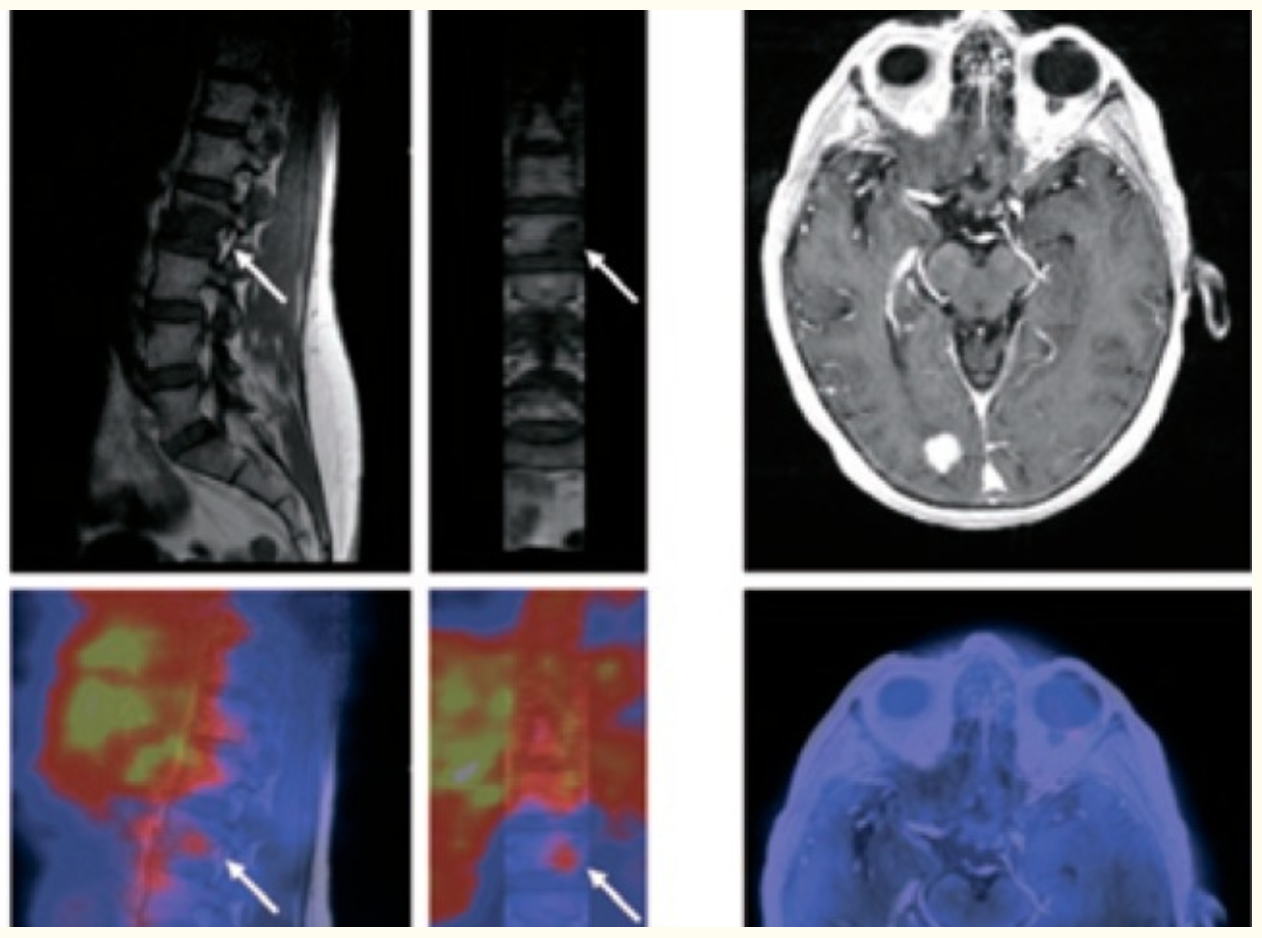

177Lu-DOTA-octreotate

Application of radiolabeled peptides for targeted therapy; 177Lu-DOTA-octreotate emits gamma and beta particle radiation, the peptide molecules bind somatostatin receptors on tumor cells and can be applied for both tumor imaging and radionuclide therapy.

Current Status of 177 Lu-PSMA Targeted Therapies and Where Will We Be In the Near Future

ESMO 2019: Preliminary Results of a Phase I/II Dose-escalation Study of Fractionated Dose 177Lu-PSMA-617 for Progressive mCRPC

Phase I/II Trial of Lutetium-177–PSMA-617 Plus Idronoxil in Metastatic Castration-Resistant Prostate Cancer

PSMA PET During Lu-177–PSMA Radioligand Therapy May Help Guide Treatment

Results of a 50 patient single-center phase II prospective trial of Lutetium-177 PSMA-617 theranostics in metastatic castrate-resistant prostate cancer

Advanced Prostate Cancer: 225-Ac-PSMA-618 Treatment

225Ac-PSMA-617 in chemotherapy-naive patients with advanced prostate cancer: a pilot study

225Ac-PSMA-617/177Lu-PSMA-617 tandem therapy of metastatic castration-resistant prostate cancer: pilot experience

Safety and Efficacy of Ac-225-PSMA-617 in mCRPC after Failure of Lu-177-PSMA